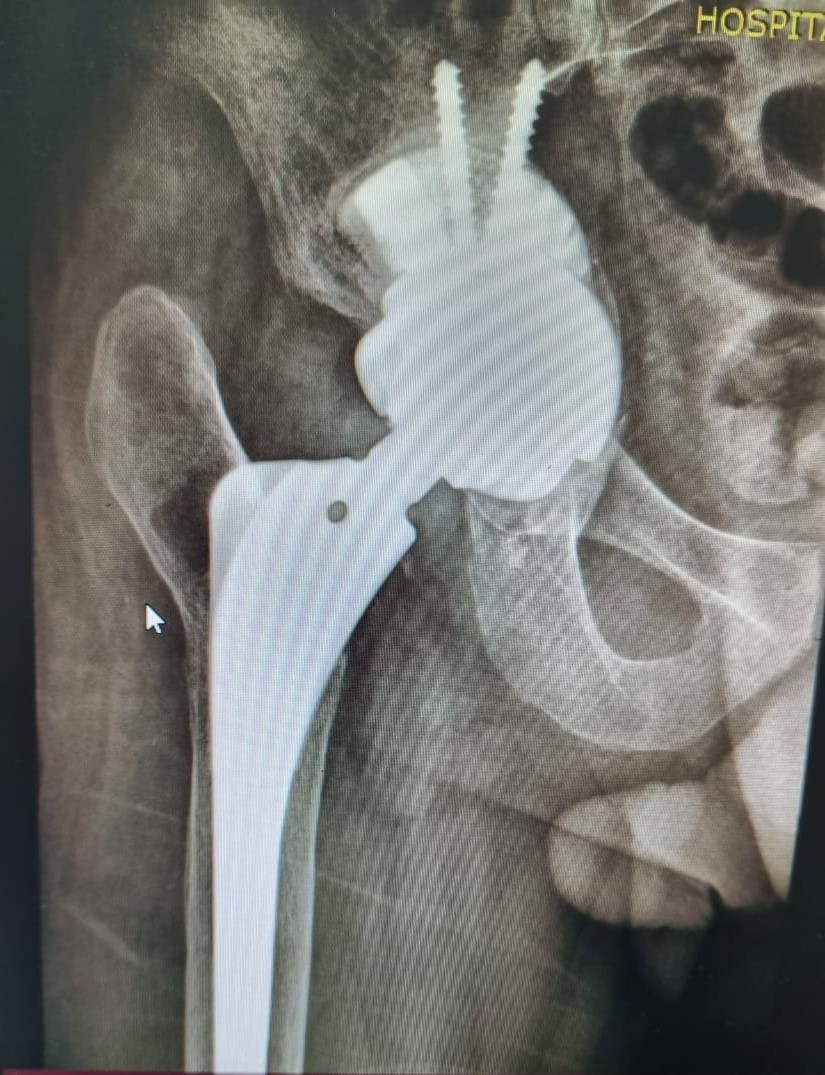

• Próteses de Quadril (Primárias  e Revisões);

• Cirurgia do Quadril;